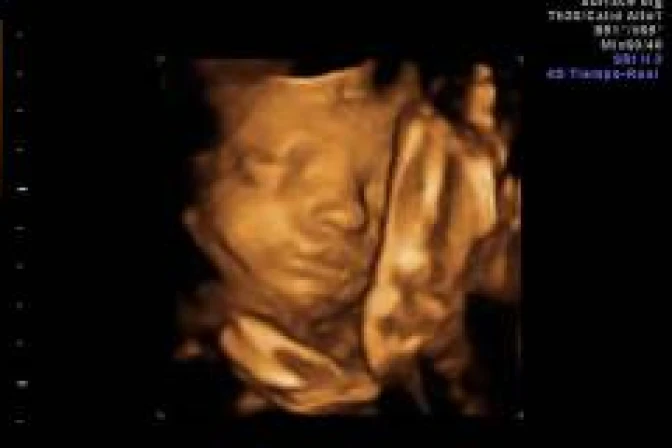

Los investigadores analizaron las secuencias de vídeo 4D de 15 fetos sanos (ocho femeninos y siete masculinos) de entre 24 a 36 semanas de gestación para examinar de cerca todos los acontecimientos en un tramo de aftosa en el feto y hallaron que más de la mitad de las aberturas de la boca observadas fueron bostezos, según publica este miércoles la revista 'Plos One'.

El bostezo se redujo desde las 28 semanas y que no hubo diferencias significativas entre niños y niñas en el bostezo frecuencia.

"Nuestro estudio longitudinal muestra que el bostezo disminuye al aumentar la edad fetal. A diferencia de nosotros, los fetos no bostezan por contagio ni por sueño, sino que la frecuencia de los bostezos en el útero puede estar relacionado con la maduración temprana del cerebro en la gestación", Nadja Reissland, del Departamento de la Universidad de Durham de Psicología.

Así, Reissland concretó que teniendo en cuenta que la frecuencia de bostezos en la muestra de fetos sanos se redujo desde las 28 semanas a 36 semanas de gestación, parece que el bostezo y la apertura bucal tener están relacionados con la maduración de la gestación, por ejemplo del sistema nervioso central.